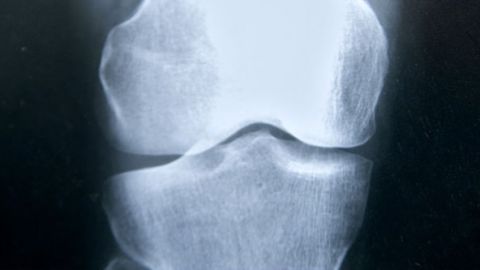

Los nuevos fármacos para tratar la osteoporosis serán capaces de fabricar hueso nuevo y más resistente. Esta es uno de los temas que mas de medio millar de especialistas médicos están abordando en el Congreso de la Sociedad Española de Investigación Ósea y Metabolismo Mineral que se estácelebrando en Elche.

Los especilistas aseguran que los progresos en la investigación de estos farmacos avanzan a buen ritmo y ya están dadno protemetedores resultados. Y es que la osteoporosis esta siendo el principal eje de debate en este encuentro médico incidiendo, además de su tratamiento, en aspectos como la necesidad de aumentar la aportación de Vitamina D a nuestro organismo o la influencia de una dieta rica en pescado azul, verudras de hoja verde y frutos secos para incrementar el aporte de calcio.

Se estima que la osteoporosis afecta en nuestro país a una de cada cuatro mujeres mayores de 50 años.